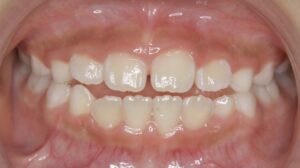

↑ 隙間が自然と埋まることも多いとされています

「いわゆる“醜いアヒルの子”期(Ugly Duckling stage)」とは、大人の歯と子供の歯が混ざった小学生の時期、医学的には混合歯列期において、上あごの中央付近、左右の永久中切歯が外側に傾斜することで、中央に隙間(正中離開/diastema)が生じる現象を指します。

文献的には、この隙間(正中離開)は混合歯列期に比較的高頻度にみられ、上顎の側切歯・犬歯が萌出を進める段階で自然に閉じていくことが多い、という報告が古くからあります。

そのため、基本的な方針としては「この時期(混合歯列期)では、まず経過観察でも良い場合が多い」というスタンスをとることが一般的です。

↑ 上記のように永久歯が出てくることで、隙間は減ってくることが多いとされています